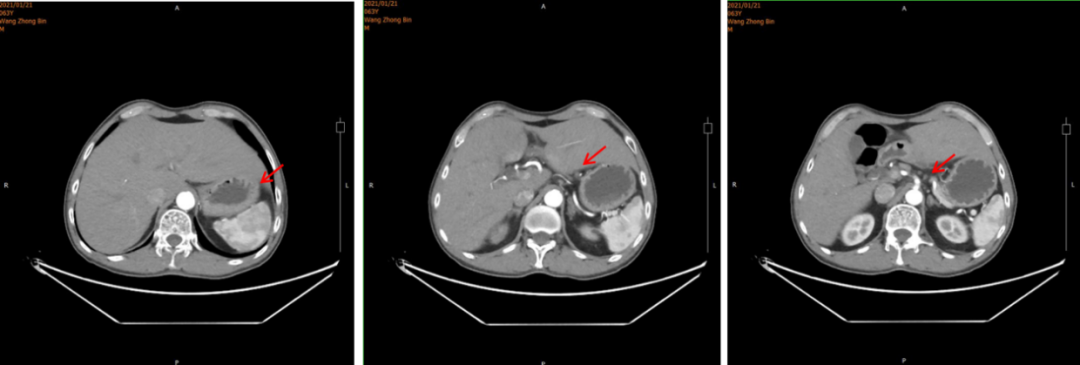

2021年1月21日腹部CT:胃窦癌征象,伴胃周、腹膜后增大淋巴结,请结合临床;肝右叶肝内胆管结石或钙化灶;左侧肾上腺强化不均。

图1.腹部CT